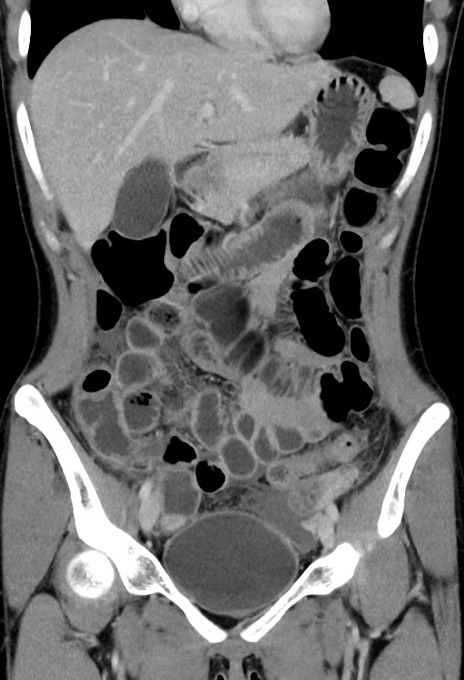

症例17(冠状断像)

【症例】20歳代女性

【主訴】嘔吐、下腹部痛

【現病歴】昨日夕食後に嘔吐し下腹部痛が出現。本日になっても嘔吐持続し改善しないため来院。

【身体所見】意識清明、BT 37.2℃、BP 108/67mmHg、腹部:平坦、やや硬、下腹部正中から右にかけて圧痛あり、反跳痛軽度あり、tapping pain(+)。

【データ】WBC 13600、CRP 14.94